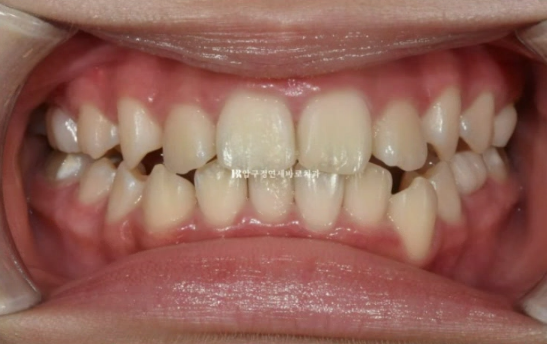

24.07

그리고 추가장치를 4달간 더 낀 후의 모습입니다.

중심선은 잘 맞아졌습니다.

교합도 좋습니다.

23.08~24.07

무엇보다 한쪽의 3급 어금니 교합관계는 1급이 되었습니다.